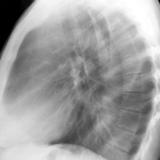

RLL Collapse  1 Lateral

Date: 02/28/2004

Views: 3258